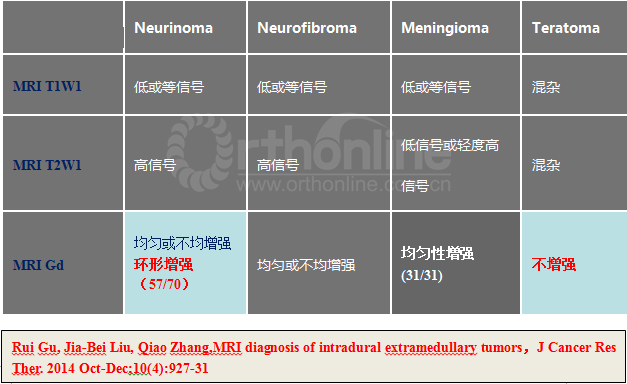

二、影像学表现:

X线平片和CT检查均需要依据钙化或肿瘤引起的明显骨质改变而检出病灶,阳性率较低,但是有助于了解脊柱的稳定程度、对手术方案的制定提供帮助;脊髓造影为有创性检查,通过肿瘤与造影剂的作用(如表现为充盈缺损等)对肿瘤的定位诊断有一定的帮助,但是对于肿瘤定性存在困难。MRI对椎管内软组织分辨率高并且能够避免骨骼的伪影,根据不同肿瘤相对特征性的MRI表现可以获得较为准确可靠的定位及定性诊断,有利于术前制定合理的手术方案。

神经鞘瘤(Neurinoma)

脊膜瘤(Meningioma)

我们回顾性分析了我院108例(111个病灶)硬膜下髓外肿瘤病例特点;神经鞘瘤69(70病灶),脊膜瘤31(31病灶),神经纤维瘤3(5病灶),畸胎瘤4(4病灶),转移性肿瘤1(1病灶)。不同肿瘤的MRI表现具有一定的特异性:

3.MRI上总结出的一些特点可以帮助术前预判;